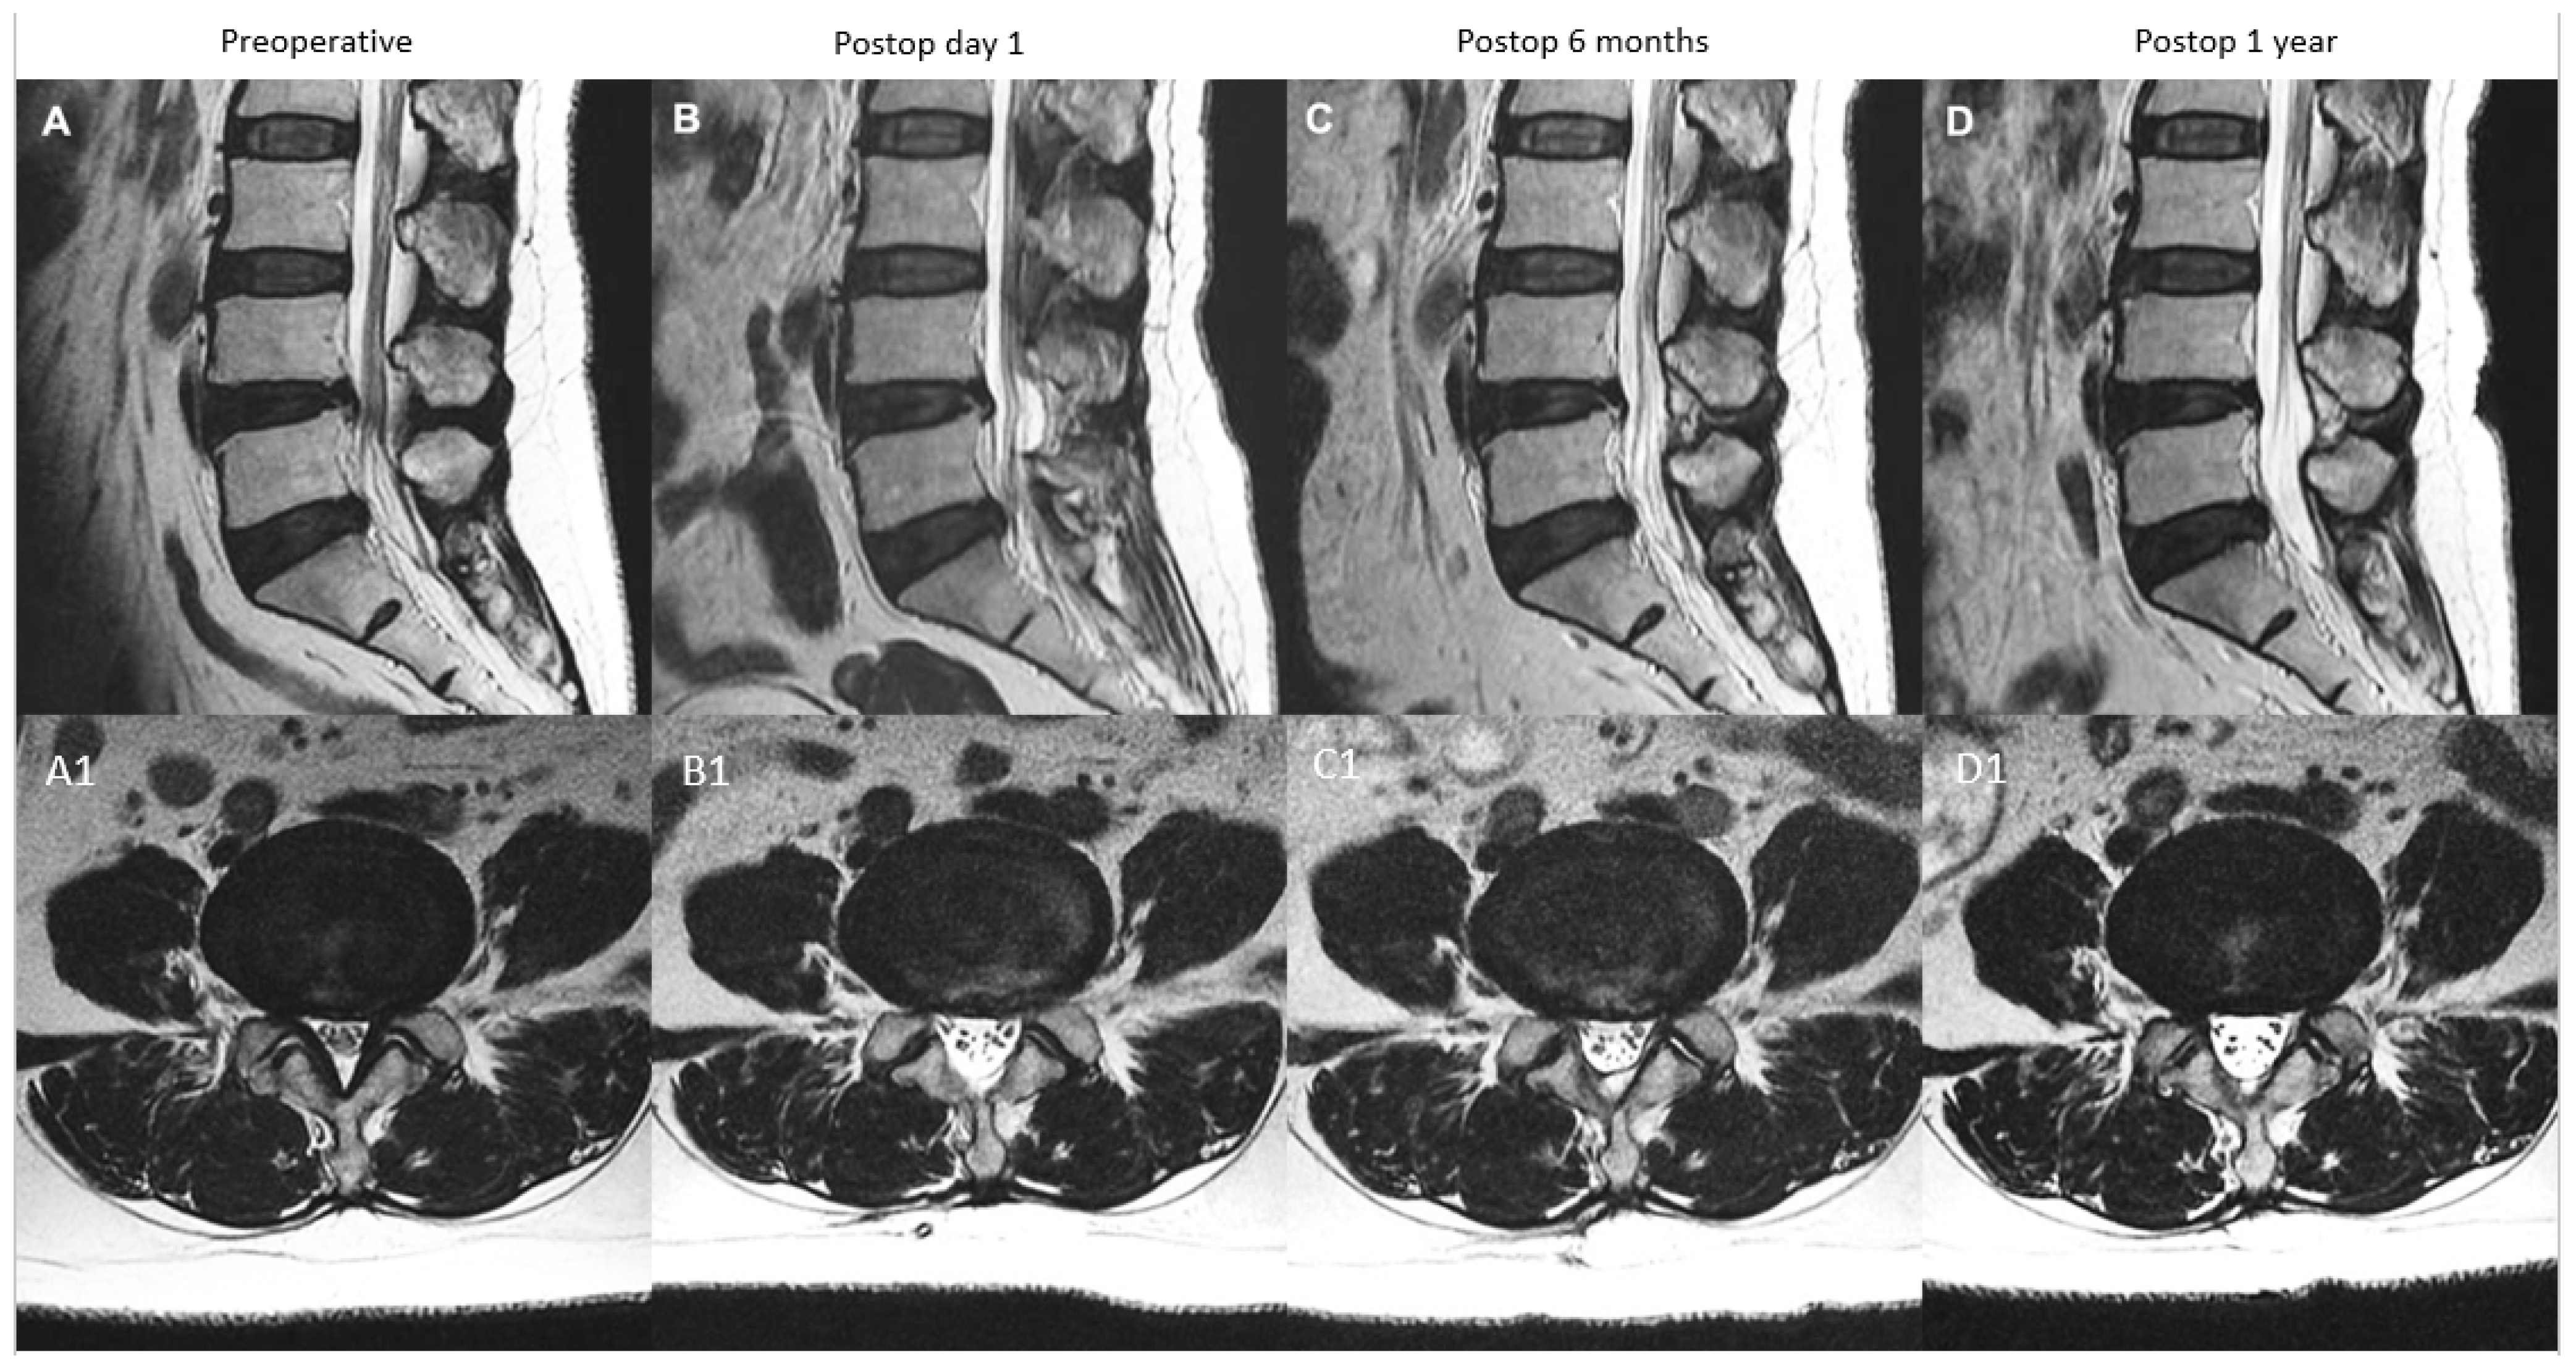

| A: Continuous Type | There is significant decompression with increased spinal canal area on postoperative day one, a modest drop at postoperative 6 months and close to postoperative 6 months value at postoperative one year | X | ≥70% X | 70–90% X (close to postoperative six months value) |

| B: Remodelling Type | There is significant decompression with increased spinal canal area on postoperative day one, a significant drop at postoperative 6 months and modest improvement at one year but less than 90% of the postoperative day one spinal canal area | X | <70% X | 70–90% X |

| C: Expansion Type | There is significant decompression with increased spinal canal area on postoperative day one, a modest drop at postoperative 6 months and significant improvement at one year with more than 90% of the postoperative day one spinal canal area | X | ≥70% X | 90–100% X |

| D: Restenosis Type | There is significant decompression with increased spinal canal area on postoperative day one, a significant drop at postoperative 6 months and minimal improvement at one year with <70% of the postoperative day one spinal canal area | X | <70% X | <70% X |